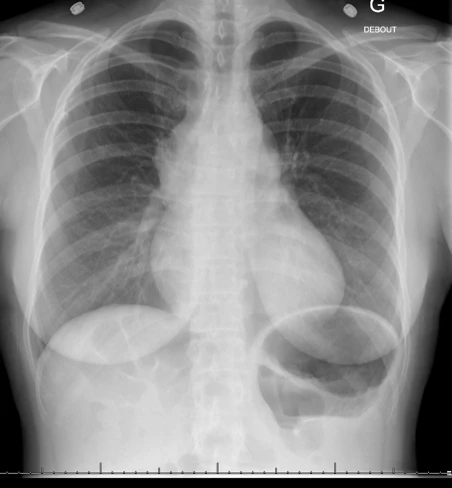

Voici sa radiographie de thorax :